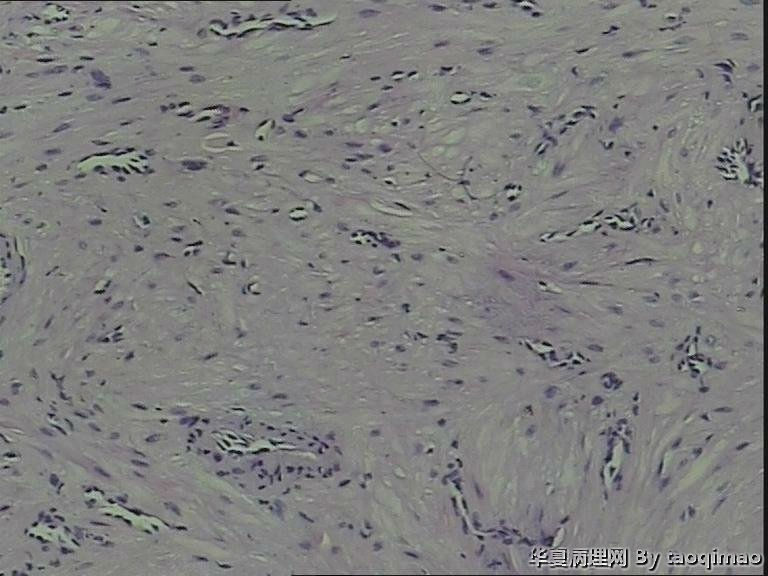

胫骨皮下结节

29岁女,发现左胫骨皮下硬结一年

灰白粟粒大组织一块,包膜完整,切面实性,质韧

纤维瘤

平滑肌血管纤维瘤。

血管平滑肌瘤